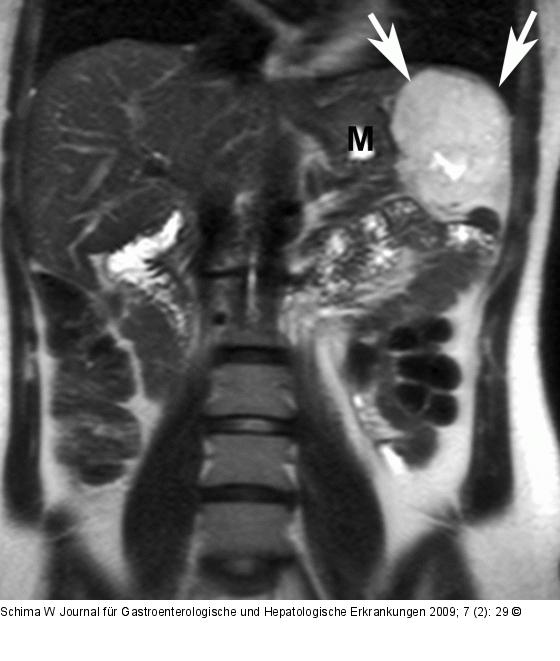

Abbildung 2: Hämangiom Die MRT in koronaler Schichtführung zeigt das typische Signalverhalten eines Hämangioms (Pfeile). Magen (M). |

Abbildung 2: Hämangiom

Die MRT in koronaler Schichtführung zeigt das typische Signalverhalten eines Hämangioms (Pfeile). Magen (M). |